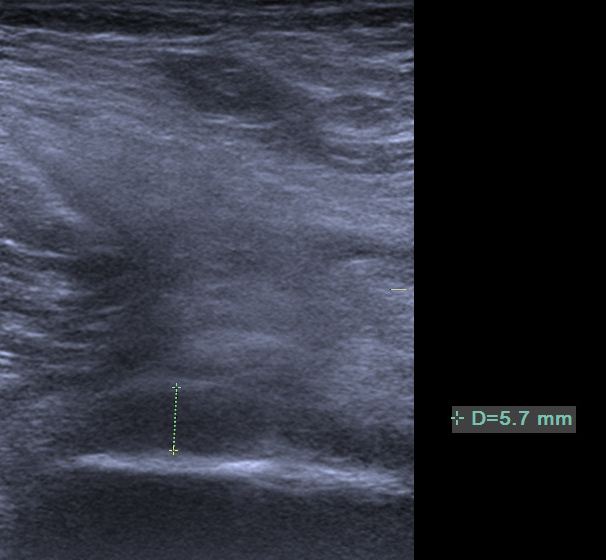

4.腋下关节囊增厚

诊断主要依靠测量肩峰下-三角肌下滑囊的厚度,其正常厚度应小于2mm,当滑囊厚度增加超过正常值时,结合临床症状及病史可初步诊断。